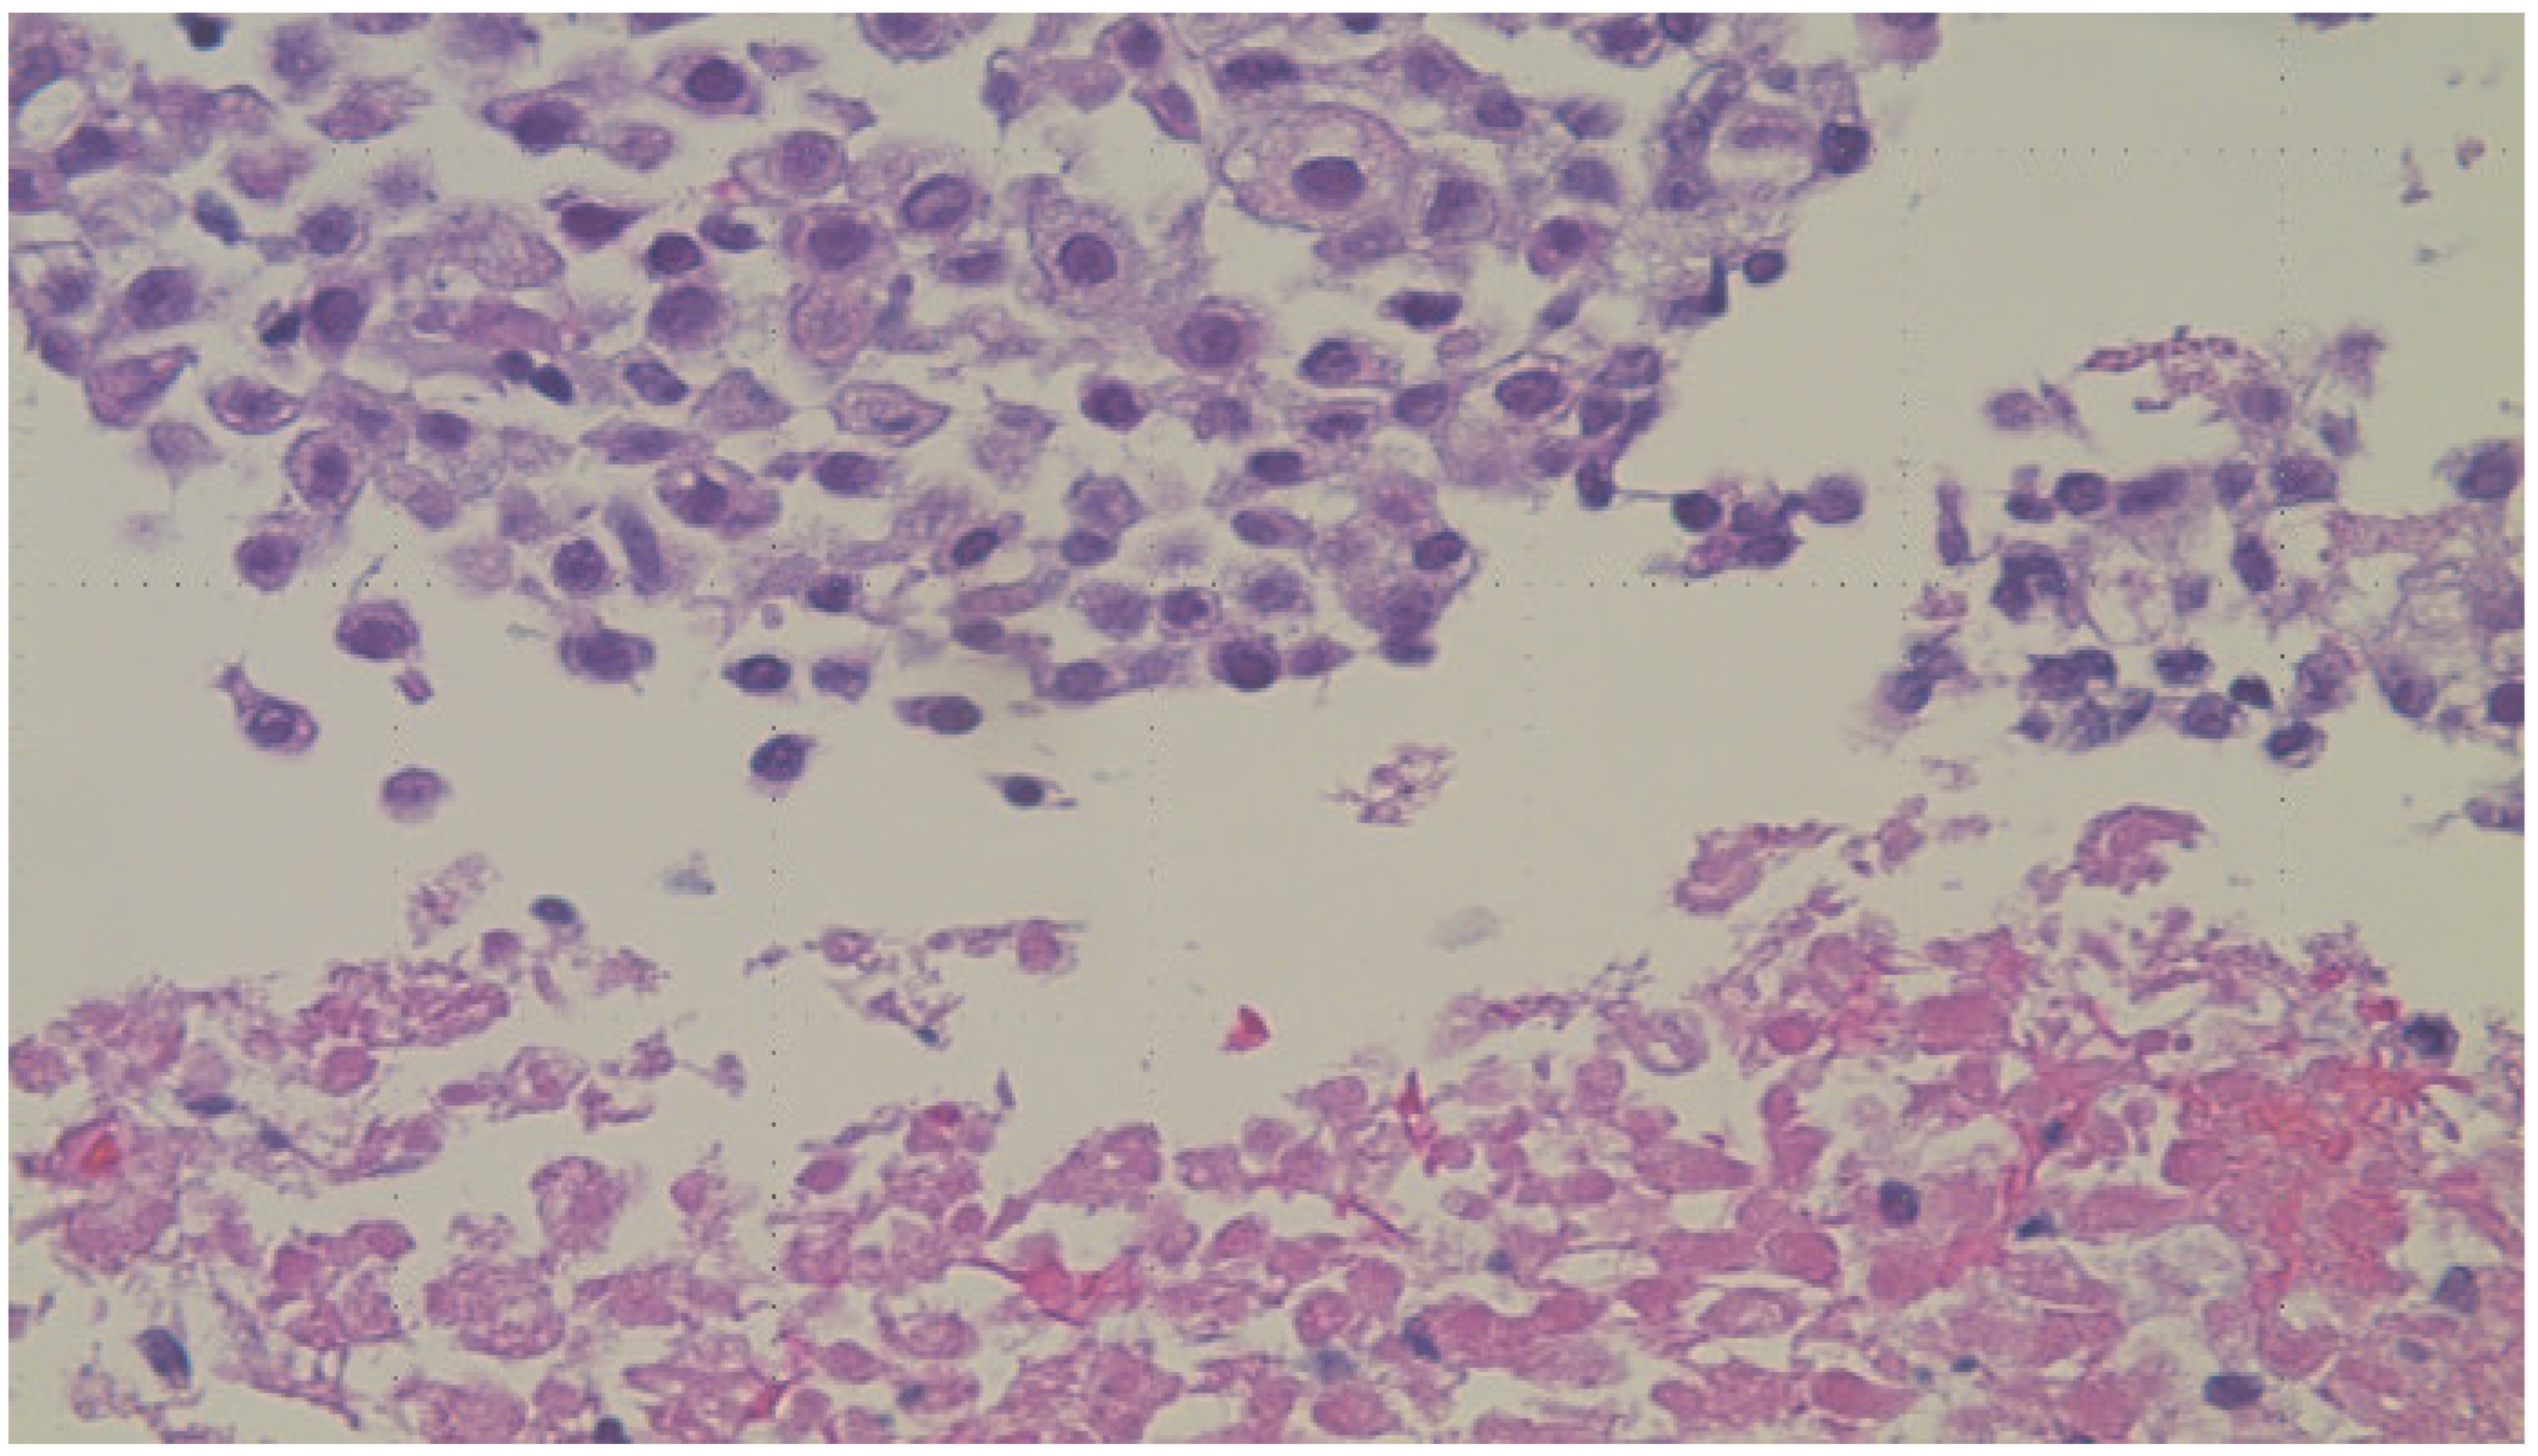

The clinical team decided to perform an ultrasound-guided fine-needle aspiration and biopsy of one of the liver lesions. Touch preparation (Figure 4: DiffQuick, 200X power field) and the biopsy (Figure 5: H&E, 100X power field) showed sheets of malignant epithelioid cells with a high nuclear-to-cytoplasmic ratio, vacuolated eosinophilic cytoplasm, areas of necrosis (Figure 6: H&E, 400X power field), and up to five mitoses per one high-power field (Figure 7: H&E, 400X power field).

Figure 4.

DiffQuick, 200X. The touch preparation of the ultrasound-guided fine-needle aspiration and biopsy of one of the liver lesions showing sheets of malignant epithelioid cells with a high nuclear-to-cytoplasmic ratio.

Figure 6.

H&E, 400X. Sheets of malignant epithelioid cells (top) with a high nuclear-to-cytoplasmic ratio, vacuolated eosinophilic cytoplasm, and areas of tumor cell necrosis (bottom).